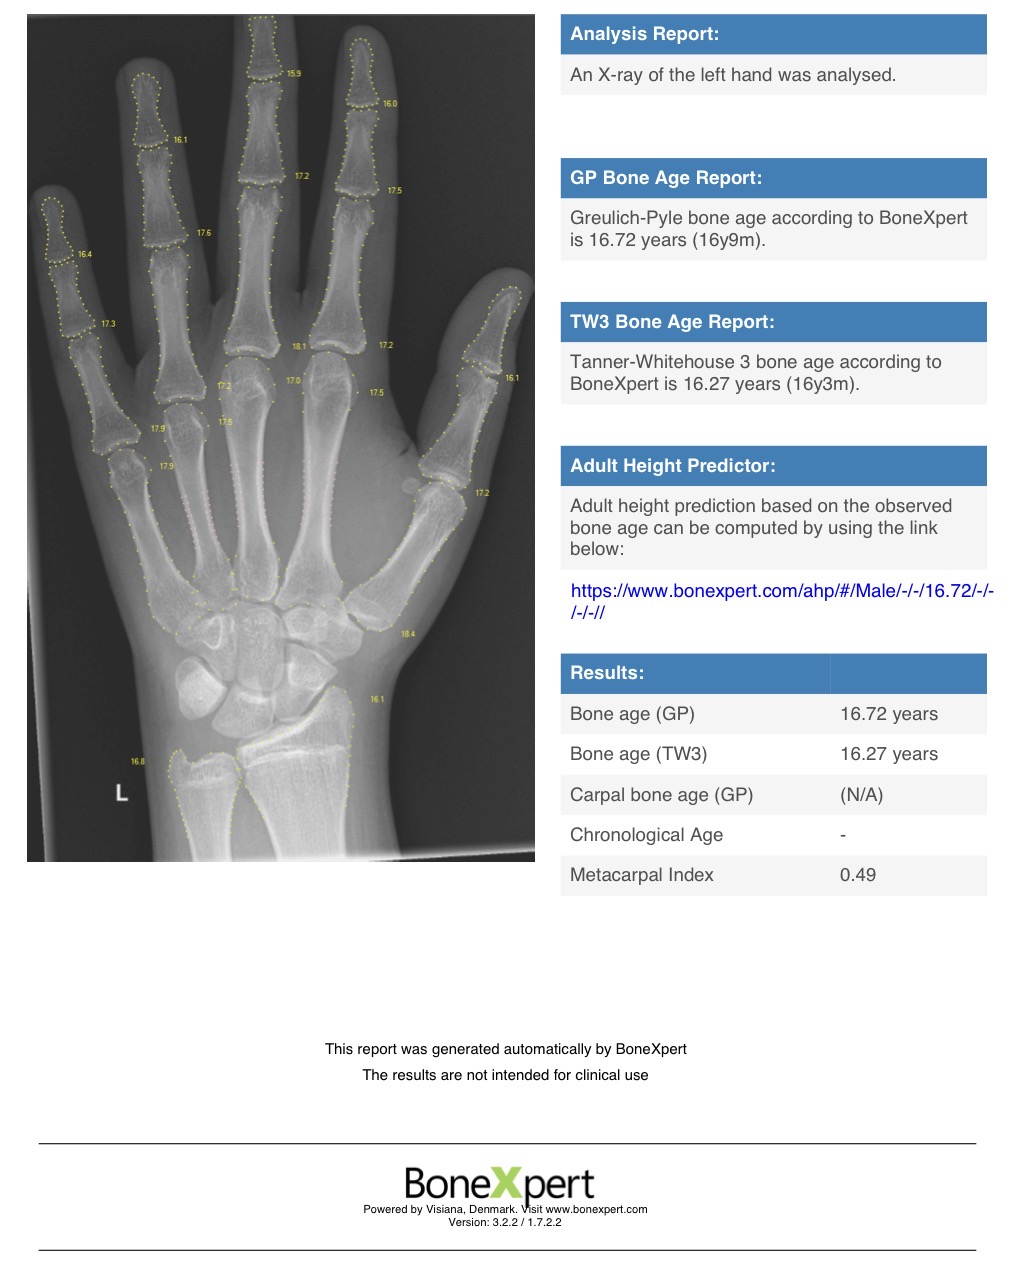

went to get a scan of my left hand. bone age shown as 16.72 by bonexpert. im 16.49. hoped for <16.5 the last 3 months or so, researching hgh etc. even bought aromasin already, but thats useless now.